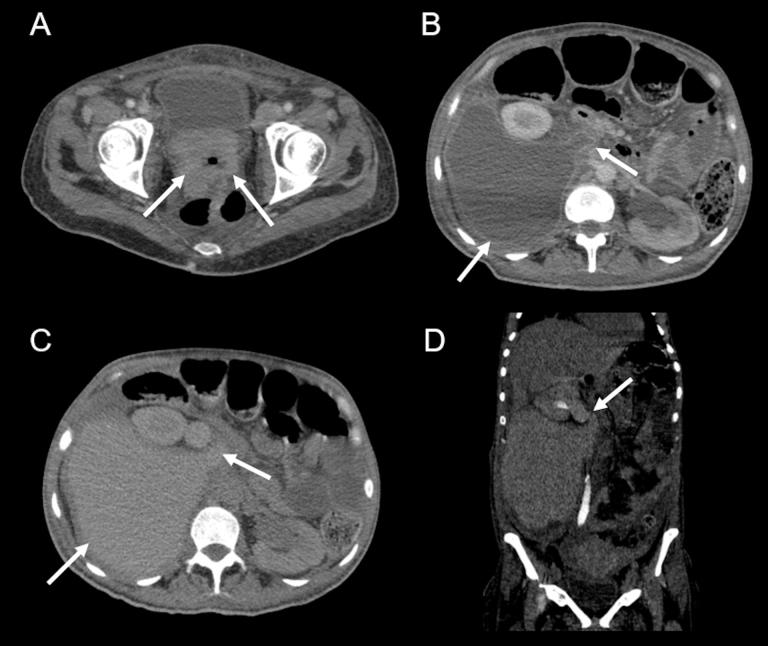

Urinoma as a complication of cervical cancer.

Abstract Image